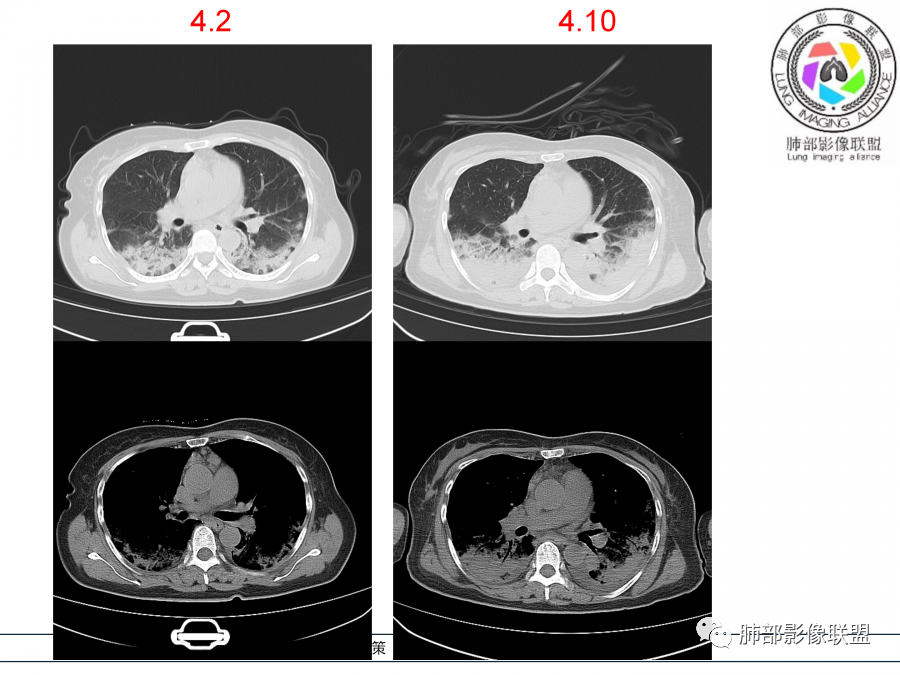

影像,第一次双肺中下叶胸膜下多发斑片状实变影,部分融合成,周围散发磨玻璃影,磨玻璃影内可见小叶间隔及小叶内间隔增厚,病变平行于胸膜,第二次间隔8天,双肺实变影明显进展,有重力作用,支气管近端堵塞,进展较快,临床有发热,血沉高,狼疮SLE阳性,考虑1:OP(机化性肺炎)2:SLE相关肺炎,建议支气管镜灌洗液病原学检测。

老年女性,咳嗽咳痰伴发热7天,白细胞不高,血沉快,降钙素原不高。其他化验未见明显异常,狼疮全套抗Ro/SSA阳性,双肺野靠近胸膜下磨玻璃实变影,支气管通畅,有充气征,沿胸膜下分布,有细网格征,7天后进展明显,实变影加重,胸膜肥厚,胸水不明显,心包少量积液?抗感染治疗无效,考虑非感染性疾病可能性大,结缔组织相关性肺病?狼疮性肺炎?机化性肺炎?鉴别病毒性肺炎。

老年女性,咳嗽咳痰发热7天。无气促。白细胞计数不高,PCT稍高,PPD(+),抗Ro/SSA阳性。CT:双肺野靠近胸膜下磨玻璃实变影,支气管通畅,有充气征,沿胸膜下分布,有细网格征。予抗生素治疗,8天后复查胸部CT见病灶范围扩大,实变影加重,胸膜肥厚,胸水不明显。抗感染治疗无效,考虑有:1.非感染性疾病:结缔组织相关性肺病,支持点:肺部CT表现为间质性炎症病变,抗RO/SSA(52)阳性;2.病毒性肺炎:患者无气促症状,可能性小;3.肺结核。

第一次双肺中下叶胸膜下多发斑片状磨玻璃及实变影,病变平行于胸膜,支气管通畅,8天后,双肺实变影明显进展范围扩大,部分支气管近端堵塞,进展较快,胸腔积液,抗感染治疗无效,考虑:非感染性疾病:结缔组织相关性肺病。鉴别机化性肺炎。

外围胸膜下,实变+GGO+网格,支气管通畅

提示间质为主病变

这病史AIP就不符合了

少量胸水,支气管无明显牵拉扩张